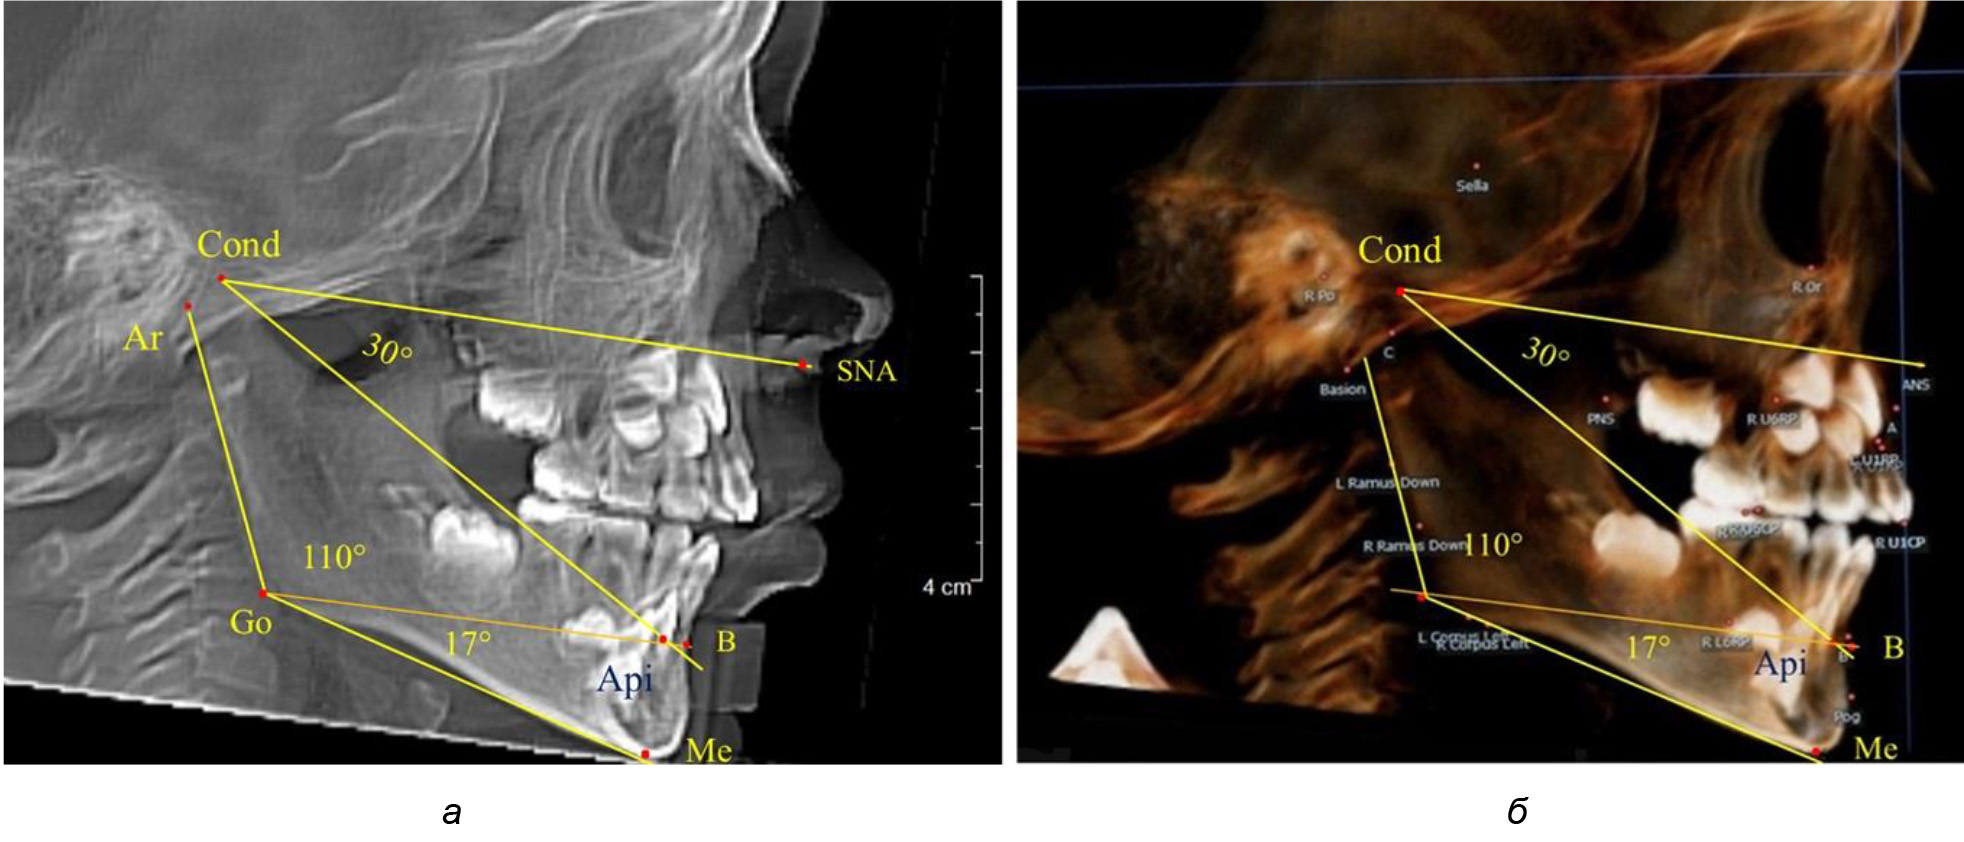

Кроме того, угол нижней челюсти Ar-Go-Me линией Go-Api делили на две составляющие. Верхняя часть угла Ar-Go-Api определяла значение альвеолярного нижнечелюстного угла, а угол Api-Go-Me определял особенности части тела нижней челюсти (рис. 1).

Рис. 1. Расположение реперных точек (а) и линий (б) для оценки угловых параметров гнатической части телерентгенограммы

При анализе ТРГ 5 детей в периоде прикуса молочных зубов отмечено, что величина основного угла гнатической части лица SNA-Cond-Api, как правило, в норме составляла около 30°, и его величина была относительно стабильной у всех обследованных детей. В то же время угол нижней челюсти и его составляющие отличались вариабельностью параметров при различных показателях нижнечелюстного угла (рис. 4).

Рис. 4. Особенности ТРГ (а) и 3D-модели (б) в периоде прикуса молочных зубов

Таким образом, в периоде молочного прикуса с оптимальными окклюзионными соотношениями, несмотря на линейные размеры в вертикальном и сагиттальном направлении, которые, безусловно, меньше параметров взрослых людей, величина основного угла гнатической части лица SNA-Cond-Api соответствовала параметрам людей с полностью сформированным физиологическим прикусом постоянных зубов. Анализируя данные рентгенограмм детей в периоде сменного прикуса, отмечено, что величина основного угла гнатической части лица SNA-Cond-Api, так же как в молочном и постоянном прикусе, в норме составляла от 28 до 32°. В то же время угол нижней челюсти и его составляющие отличались вариабельностью параметров при различных показателях нижнечелюстного угла. Достоверных различий угла гнатической части после смены нижних медиальных резцов и прорезывания первых постоянных моляров (4 ребенка) не было; происходил очередной этап подъема высоты прикуса и увеличение линейных размеров костей гнатической части, однако угловые параметры были относительно стабильны. После смены всех резцов и замены первых молочных моляров первыми премолярами (6 человек) увеличивались линейные размеры при сохранившихся угловых показателях гнатической части лица (рис. 5).